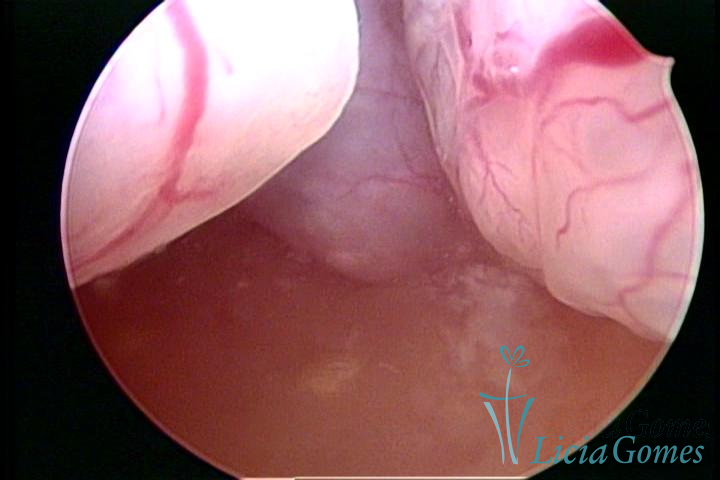

Este pode apresentar uma gama variável de aspectos macroscópicos, com aspecto pseudopolipoide; lembrando tecido cerebroide ou com reação deciduoide;a vascularização superficial é mais evidente e com vasos em formatos de saca-rolha ou espirais visualizando também a vascularização com atípias, com aumento do calibre dos vasos superficiais, pode ser encontrado também tecido em necrose, poderá haver um pequenos dendritos (papilomatoso).